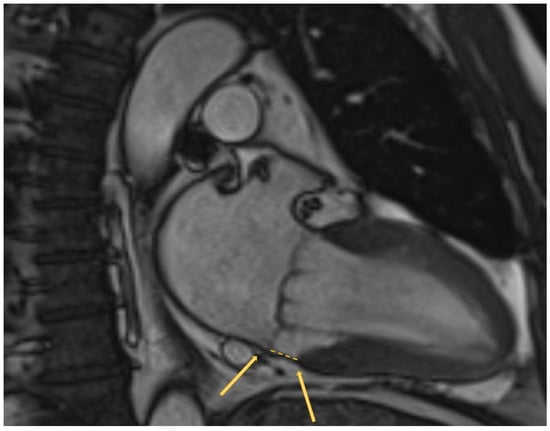

- Bennett, S.; Thamman, R.; Griffiths, T.; Oxley, C.; Khan, J.N.; Phan, T.; Patwala, A.; Heatlie, G.; Kwok, C.S. Mitral annular disjunction: A systematic review of the literature. Echocardiography 2019, 36, 1549–1558. [Google Scholar] [CrossRef]

- Toh, H.; Mori, S.; Izawa, Y.; Fujita, H.; Miwa, K.; Suzuki, M.; Takahashi, Y.; Toba, T.; Watanabe, Y.; Kono, A.K.; et al. Prevalence and extent of mitral annular disjunction in structurally normal hearts: Comprehensive 3D analysis using cardiac computed tomography. Eur. Heart J. Cardiovasc. Imaging 2021, 22, 614–622. [Google Scholar] [CrossRef]